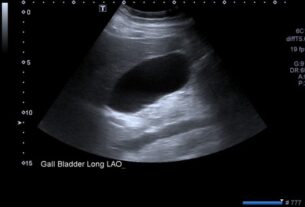

- USG Whole Abdomen Screening